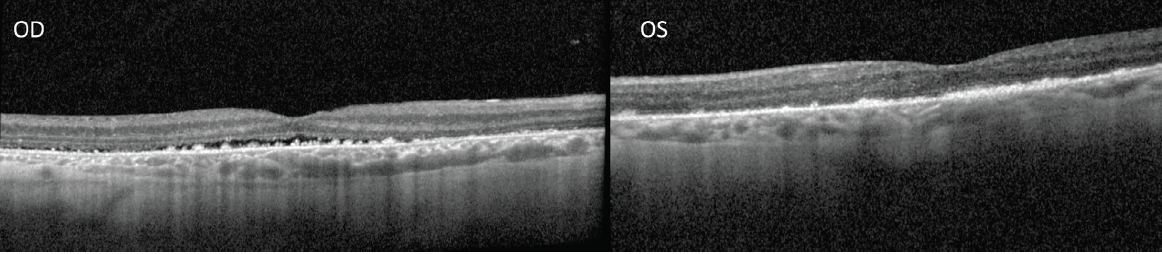

Given these findings and the patient’s variable response to steroids, it is most likely that the patient had a variant of central serous chorioretinopathy (CSCR). The oral steroids were stopped, and the patient was instructed to cease using the oxymetholone pills. At the most recent follow up visit, 2 months after stopping the oral prednisone, BCVA was 20/70 in the patient’s right eye with resolving subretinal fluid and 20/30 in the left eye with no subretinal fluid (Figure 4). Observation of the patient continues, awaiting further improvement.

<p>Figure 4. OCT was taken 2 months after the discontinuation of the patient’s steroids. OCT of the right eye (left photo) shows interval improvement in the subretinal fluid. OCT of the left eye (right photo) shows resolution of the subretinal fluid.</p>

Figure 4. OCT was taken 2 months after the discontinuation of the patient’s steroids. OCT of the right eye (left photo) shows interval improvement in the subretinal fluid. OCT of the left eye (right photo) shows resolution of the subretinal fluid.